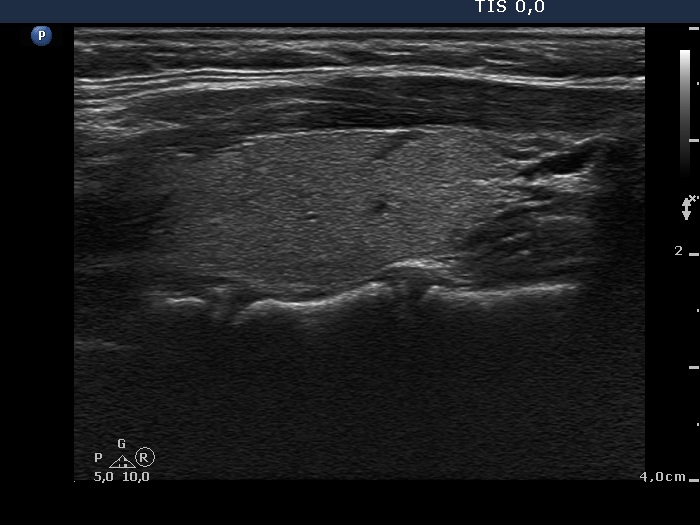

Graves' disease - Case 1080

Follow-up investigation 24 months after first examination (ultrasonographic picture 5)

Right lobe, horizontal view